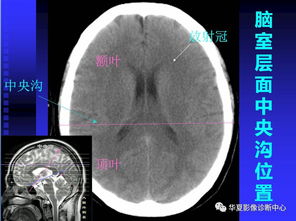

MRI檢查時采用不同的序列和參數或注射造影劑進行增強,都是 為了增加不同組織間,正常組織與病理組織間信號強度,提高診斷的敏 感性和特異性。 頭顱MRI優(yōu)勢:與CT相比,MRI有冠狀位、矢狀位和橫斷面,能更 全面準確判斷病灶的位置和性質;MRI的軟組織對比分辨率最高,圖像 清晰度高,無骨偽影,對脊髓、頡后窩、幕上病變的形態(tài)、位置、大小以及 與周邊組織的關系,有較高的腦灰質和白質對比度和組織分辨率。